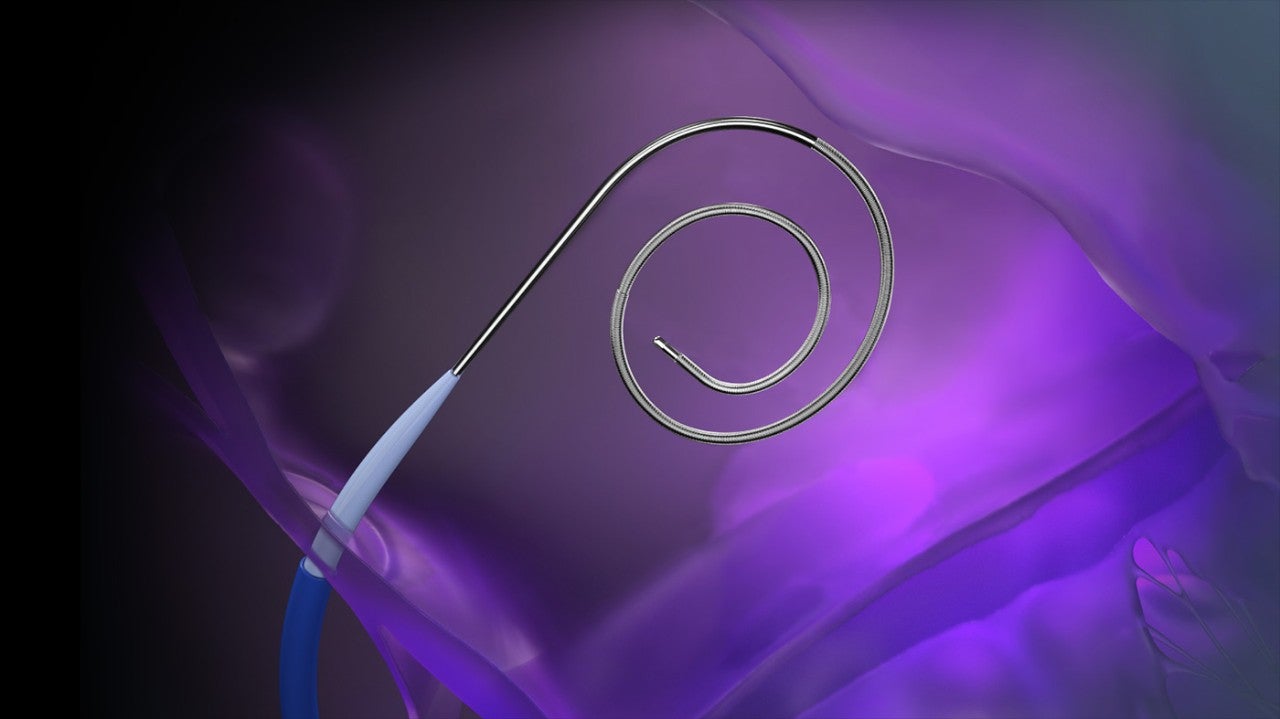

• VersaCross RF Wire (j-tip or pigtail)

VersaCross RF Wire in j-tip and pigtail configurations.

VersaCross RF Wire

RF wire length: 180 cm, 230 cm

Wire diameter: 0.035 in (0.89 mm)

Curve diameter: 9 mm (j-tip), 24 mm (pigtail)